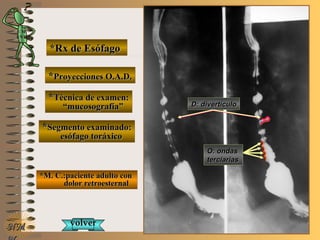

*Rx de Esófago*Rx de Esófago

**Proyecciones:Proyecciones:

**Técnica de examen:Técnica de examen:

**Segmento examinado:Segmento examinado:

*M. C.:paciente adulto con*M. C.:paciente adulto con

dolor retroesternaldolor retroesternal

O.A.D.O.A.D.

““mucosografía”mucosografía”

esófago toráxicoesófago toráxico

A-A-El examen es normal o patológico?El examen es normal o patológico?

Examen patológico de esófago toráxico con téc-Examen patológico de esófago toráxico con téc-

nica de mucosografía y en proyecciones O.A.D.nica de mucosografía y en proyecciones O.A.D.

B-B-La patología es congénita o adquirida?La patología es congénita o adquirida?

Patología adquiridaPatología adquirida

C-C- Dicha patología es orgánica, funcional o mixta?Dicha patología es orgánica, funcional o mixta?

Patología adquirida funcionalPatología adquirida funcional

D-D-Puede describir la o las imágenes patológicas?Puede describir la o las imágenes patológicas?

Se identifican ondas terciarias, no propulsivas queSe identifican ondas terciarias, no propulsivas que

enlentecen el traslado del bolo baritado; tambiénenlentecen el traslado del bolo baritado; también

se distingue una imagen diverticular en borde an-se distingue una imagen diverticular en borde an-

terior de tercio medio de esófago toráxicoterior de tercio medio de esófago toráxico